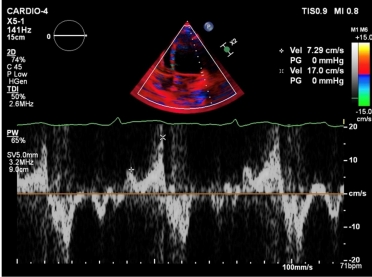

TTE was performed. The LV had a normal size, however, left ventricular ejection fraction (LVEF) was mildly impaired (48%) with mild longitudinal dysfunction (GLS -16,6%). The mitral valve appeared thickened and redundant, with bi-leaflet prolapse and mild regurgitation. MAD was seen, with a length of 4-5mm measured in mid-systole.

Tissue Doppler imaging (TDI) of the lateral wall revealed a second systolic peak, with a velocity of 17cm/s. Through speckle-tracking analysis, a double peak strain pattern is seen on the basal infero-lateral wall (orange arrows).